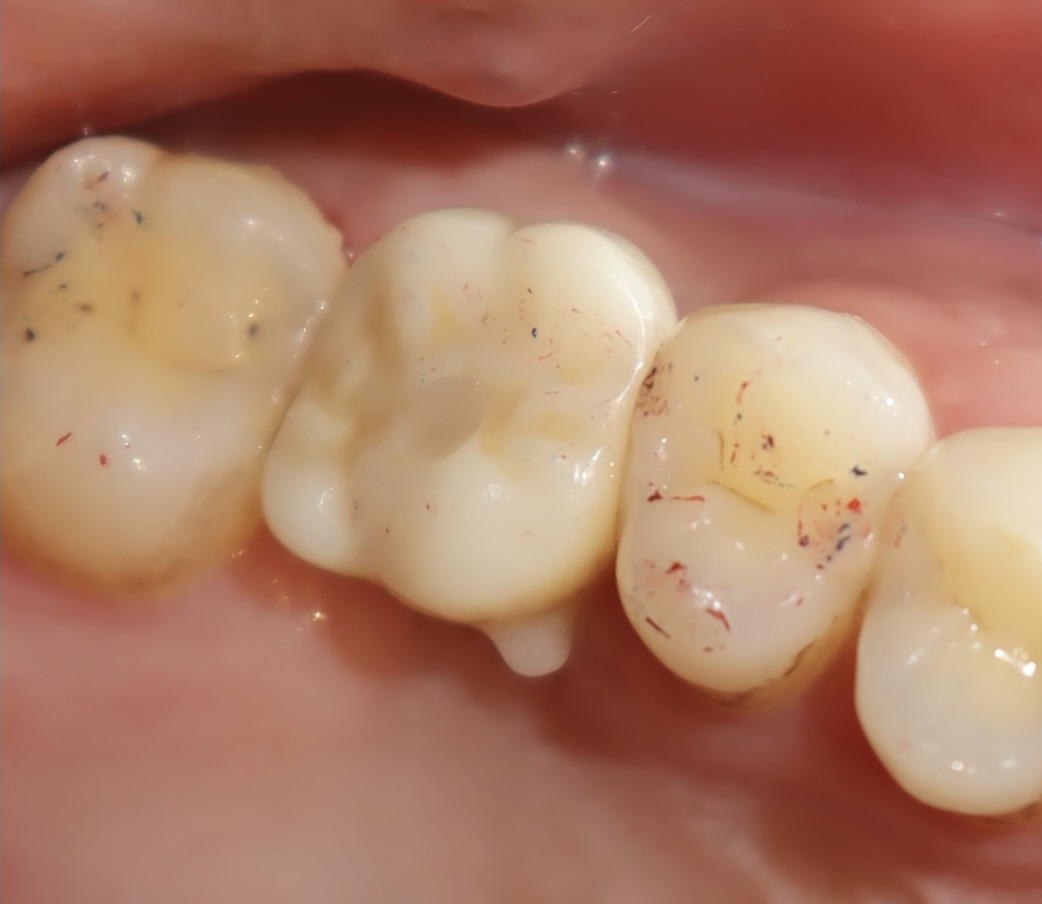

術後照片